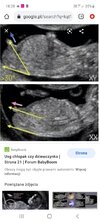

Hej Dziewczyny. Mam prośbę. Moglybyscie zerknac czy wedlug Was to chlopak czy dziewczynka 🙉. Bylam dzis u lekarza, ale nie jest pewien i nie chcial mowic. Mowi ,ze u chlopca wyrostek idzie do gory,a u dziewczynek ku dołowi 🤔🤔